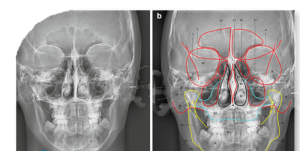

رادیولوژی سفالومتری یکی از روشهای تخصصی در حوزه رادیولوژی دهان، فک و صورت است که برای بررسی دقیق ساختار استخوانی و بافت نرم ناحیه سر و صورت استفاده میشود. این نوع تصویربرداری بیشتر در ارتودنسی و جراحیهای فک کاربرد دارد، زیرا امکان ارزیابی دقیق روابط فکی، زاویهها و تناسب اجزای صورت را فراهم میکند. در سفالومتری با دستگاههای دیجیتال پیشرفته و کمترین میزان اشعه انجام میشود تا بیمار در شرایط ایمن و با کیفیت بالای تصویر تحت بررسی قرار گیرد.

در این روش، تصویر جانبی یا قدامی-خلفی از سر بیمار تهیه میشود که شامل جزئیات کامل استخوانهای فک، دندانها و حتی برخی بافتهای نرم صورت است. متخصصان ارتودنسی از نتایج رادیولوژی دهان، فک و صورت به روش سفالومتری برای طراحی طرح درمان، پیشبینی نتایج ارتودنسی و بررسی تغییرات پس از درمان استفاده میکنند. کیفیت بالای تصاویر در رادیولوژی دکتر بصیری به پزشکان کمک میکند تا با دقت بیشتری تصمیمگیری کنند.

ویژگیهای رادیوگرافی سفالومتری:

تصویربرداری از نیمرخ:

سفالومتری معمولاً به صورت جانبی (از نیمرخ) انجام میشود، به این معنی که تصویر از کنار سر گرفته میشود.

هان و فمتصویر دقیق از ساختارها:

این روش تصویربرداری، جزئیات دقیقی از استخوانها، دندانها و بافتهای نرم را نشان میدهد.

آنالیز و اندازهگیری:

تصاویر سفالومتری قابلیت اندازهگیری و تجزیه و تحلیل دقیق زوایا و فواصل بین ساختارهای مختلف را دارند.

مقایسه با مقادیر استاندارد:با مقایسه این اندازهگیریها با مقادیر استاندارد، میتوان مشکلات و انحرافات از حالت طبیعی را تشخیص داد..